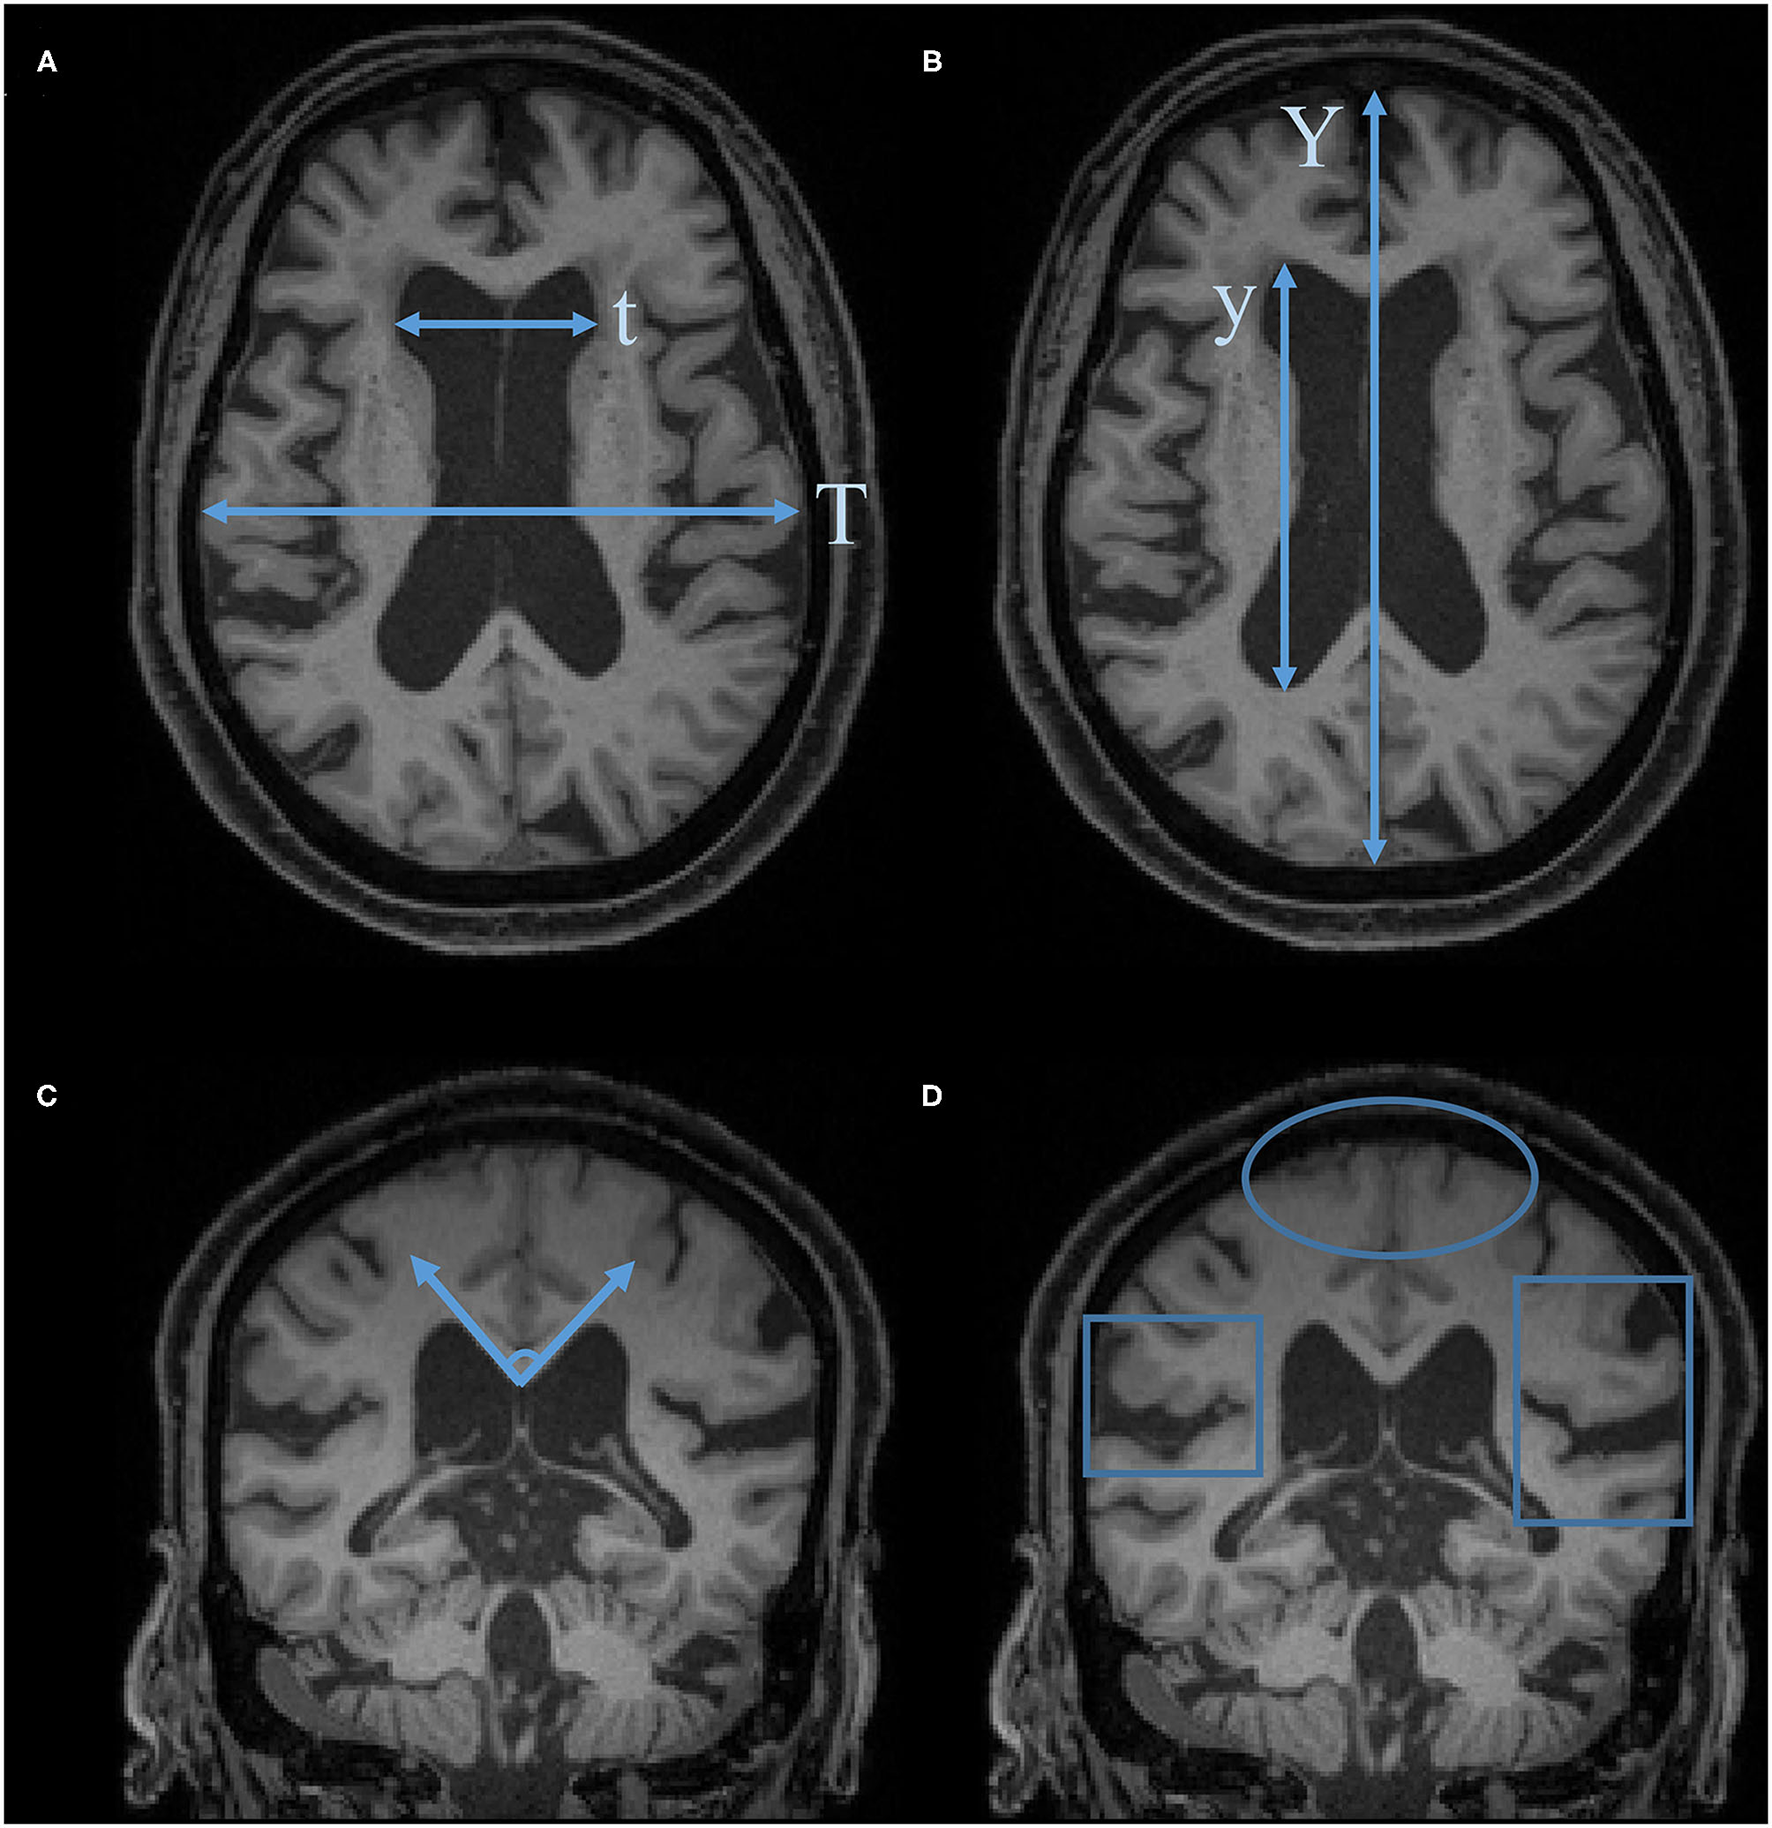

Figure 2

Characteristic imaging findings of NPH. (A) Evans Index (EI) = t/T. (B) Anteroposterior diameter of the lateral ventricle index (ALVI) = y/Y. (C) Callosal angle. (D) Disproportionately enlarged subarachnoid space hydrocephalus (DESH): Sylvian fissure enlargement and tight high-convexity effacement are present.